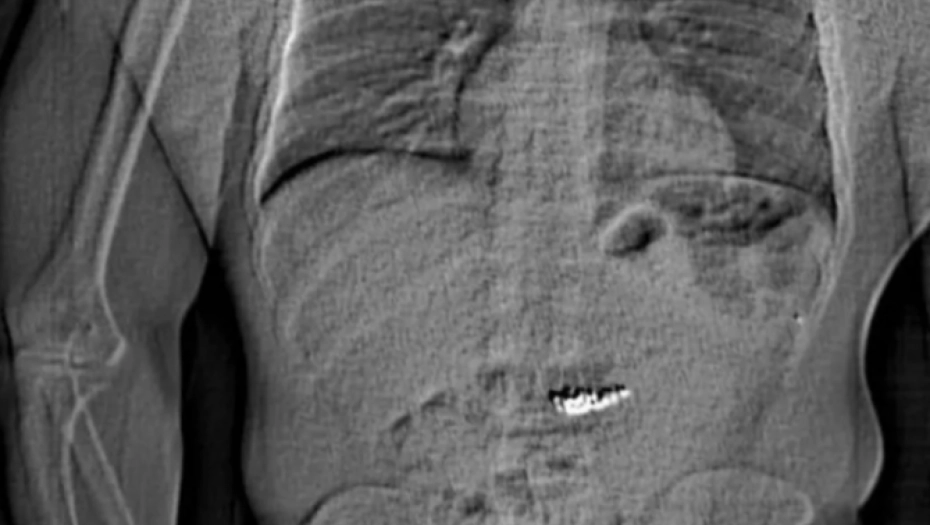

Policija je kasnije objavila rendgenski snimak na kome se vidi deo abdomena sa neobičnim predmetom unutra.